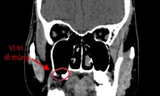

Kết quả MRI cho thấy bé bị thoát vị tủy mỡ kèm tủy bám thấp. Hình ảnh siêu âm tim và bụng ghi nhận, bệnh nhi bị đảo ngược hoàn toàn phủ tạng và có tim nằm bên phải lồng ngực nhưng các chức năng của tim ổn định, não không phát hiện bất thường.

Tình trạng phủ tạng đảo ngược có thể không làm ảnh hưởng đến sự phát triển của bệnh nhi. Tuy nhiên, bệnh lý thoát vị tủy mỡ và tủy bám thấp khiến phần tủy sống và màng tủy lộ ra ngoài có thể khiến trẻ bị liệt hai chân, rối loạn cảm giác, rối loạn cơ tròn, mất kiểm soát tiểu tiện và đại tiện. Tình trạng tủy bám thấp còn khiến tủy bị kéo căng theo thời gian, làm suy giảm vận động và cảm giác tiến triển, dẫn tới teo cơ, biến dạng cột sống hoặc cong vẹo cột sống.

Do toàn bộ cấu trúc nội tạng của bệnh nhi bị đảo ngược, các bác sĩ phải điều chỉnh toàn bộ thao tác. Ê kíp bác sĩ phải định hướng giải phẫu “ngược” so với bình thường để tránh nhầm lẫn, đặc biệt khi xử lý vùng tủy sống và mô thần kinh.